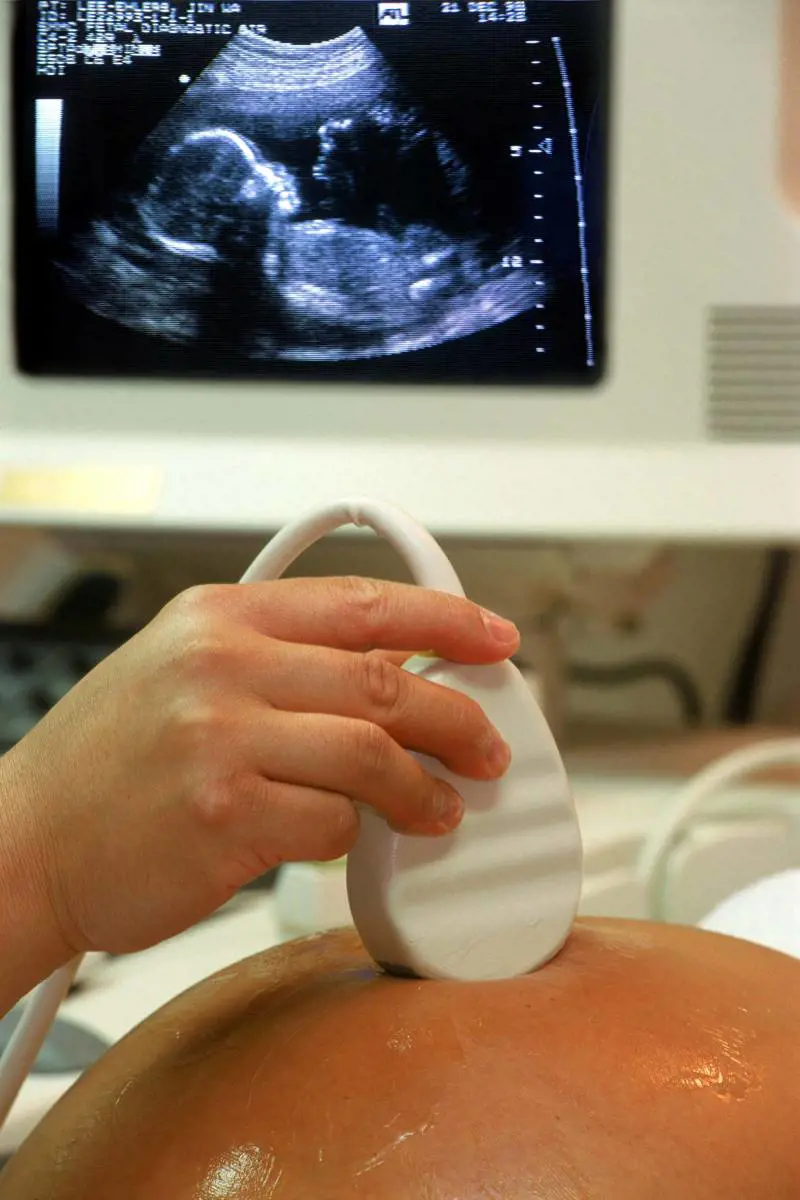

La diagnosi errata La vicenda riguarda un errore negli esami diagnostici prenatali nel 1999 quando la coppia mise al mondo una bambina affetta da ceroide lipofascinosi neuronale infantile, rarissima patologia. I problemi dei coniugi, assistiti dagli avvocati Luigi Comini e Filippo Paolini del Foro di Lanciano (in provincia di Chieti), iniziarono nel 1993, quando nacque il primogenito. Dopo pochi mesi dalla nascita il piccolo mostrò una lunga serie di deficit psichici e motori e venne sottoposto a vari esami e accertamenti all’ospedale Bambin Gesù di Roma.

Gli esami al Bambin Gesù La diagnosi dei sanitari romani fu gravissima: ceroide lipofascinosi neuronale infantile, di cui madre e padre erano portatori sani. In ogni caso i medici diedero speranza alla coppia. Attraverso particolari esami molecolari avrebbero potuto tentare una nuova gravidanza e il bambino sarebbe potuto nascere sano. Ma il primo tentativo, nel 1996, andò male e la donna fu costretta ad abortire. Tre anni dopo, nel 1999, la villocentesi diede un risultato favorevole e a settembre nacque una bambina. A 18 mesi, però, anche lei mostrò i segni della gravissima di cui era affetto il fratello, che nel frattempo morì.